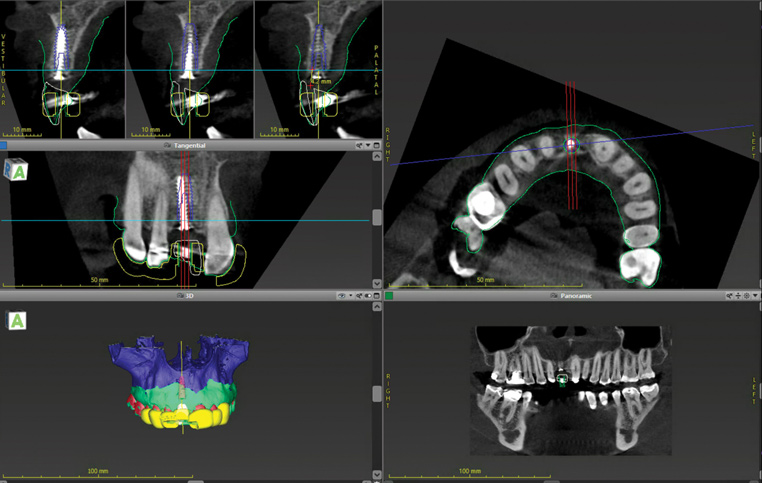

(7.) Pretreatment CBCT scan.

Figure 7

A 56-year-old female patient was referred for the evaluation of tooth No. 8 (Figure 4 and Figure 5). A periapical radiograph indicated that the tooth had undergone apicoectomy and received an excessively long post (Figure 6), and a cone-beam computed tomography (CBCT) scan of the site revealed a lack of buccal plate bone (Figure 7).

(14.) Three-dimensional implant treatment planning.

Figure 14